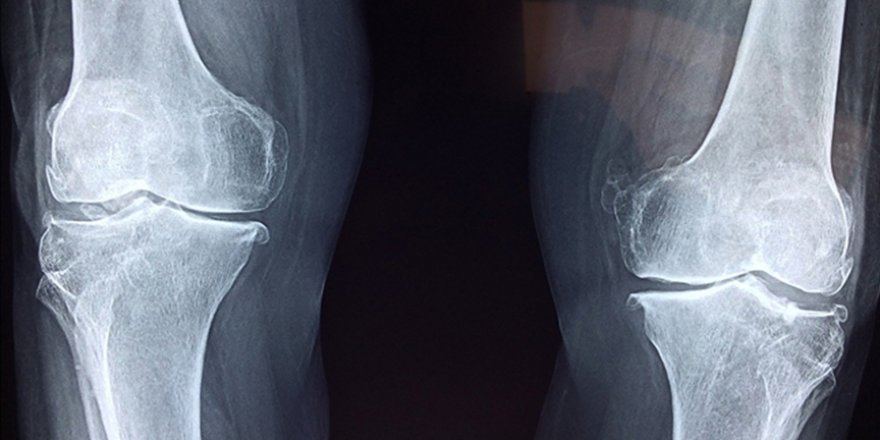

"Eklem ve kemik rahatsızlıklarında ağrı ve iltihabı azaltıyor"

"Bilimsel çalışmalar, vücudun ihtiyacı olan kolajenin, morina ve gelincik balıklarının derilerinden elde edilebildiğini gösterdi. Morina balığı içerdiği prolin, histidin, glisin ve hidroksiprolin aminoasit zincirleri ile özellikle eklem ve kemikler için eşsiz bir fayda sunar. Bu aminoasitler sayesinde kıkırdak onarımı için çok etkili olduğu bilinen kolajen peptitler, aynı zamanda ağrı ve iltihaplanmayı azaltmada da önemli rol oynar. Yapılan çalışmalarla morina balığından elde edilen kolajen peptitlerin eklem ve kemik rahatsızlıklarında ağrı ve iltihabı azaltıp kıkırdak dokusunu yenilediği, iltihap azaltıcı özellikleri sayesinde akne ve selülit tedavilerine destek olduğu, nemlendirme ve kırışıklık önleyici özellikleriyle yaraların kapanmasını hızlandırıp iz oluşumunu engellediği bulgularına ulaşıldı."